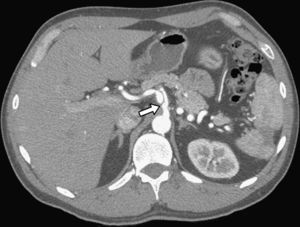

Un hombre de 64 años de edad con antecedentes de hipertensión arterial, hipercolesterolemia, asma, coronariopatía e infarto de miocardio, se presentó en el servicio de urgencias con dolor abdominal epigástrico y diarrea no sanguinolenta, de inicio súbito. En la exploración física, no se identificaron signos de peritonitis. Los datos de laboratorio revelaron leucocitosis con un recuento de 15.000/mm3. La TC abdominal con contraste demostró una disección aislada de la arteria mesentérica superior (AMS) con trombosis parcial que provocaba una estenosis del 40-50% (fig. 3). No se detectó la presencia de líquido libre o edema intestinal. Los hallazgos de la angiografía selectiva practicada al ingreso sugerían la presencia de una disección de la AMS, que no limitaba el flujo, y trombosis de la falsa luz. Se instauró dieta absoluta y perfusión de heparina sódica. El dolor abdominal y la diarrea se resolvieron al cabo de 2 días. Fue dado de alta en tratamiento con warfarina y aspirina. La TC de control efectuada a los 6 meses demostró un engrosamiento residual mínimo de la pared anterior de la AMS proximal sin signos de disección o estenosis residual (fig. 4). Se interrumpió el tratamiento con warfarina y se continuó con aspirina. Durante el año de seguimiento el paciente ha permanecido asintomático.